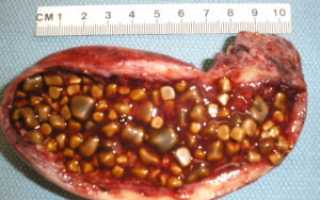

Одестон при камнях в желчном можно ли применять Одестон – лекарственное средство, которое входит в группу препаратов для терапии патологий...